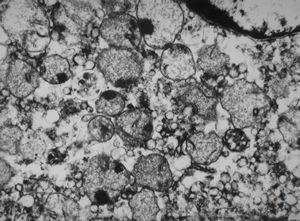

F,7m. | giant cell hepatitis